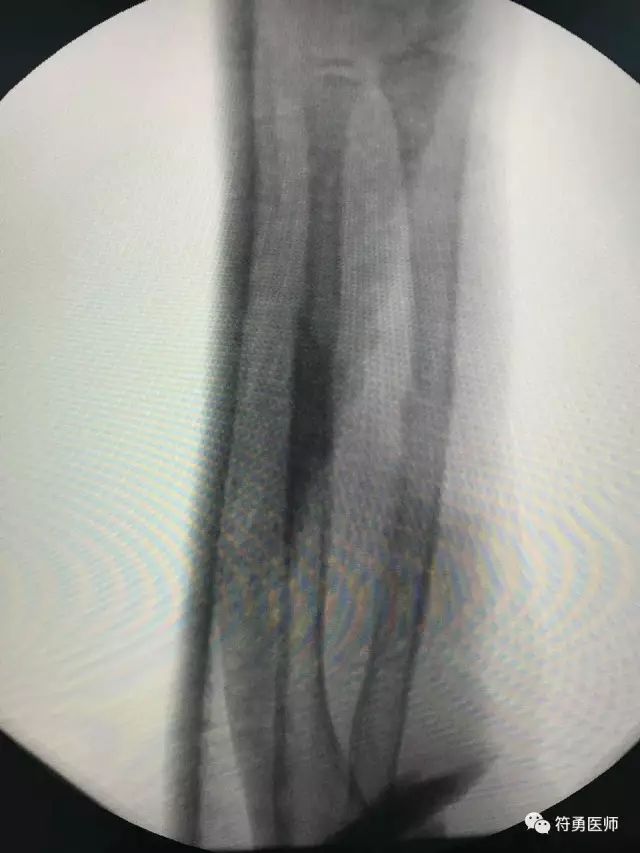

上图:摔伤后前臂骨折错位

上图:摔伤后第一次找水师接骨后仍然错位,孩子受罪疼痛折腾

上图:摔伤后第一次找水师接骨后仍然错位,几乎等于没有接,孩子受罪疼痛折腾